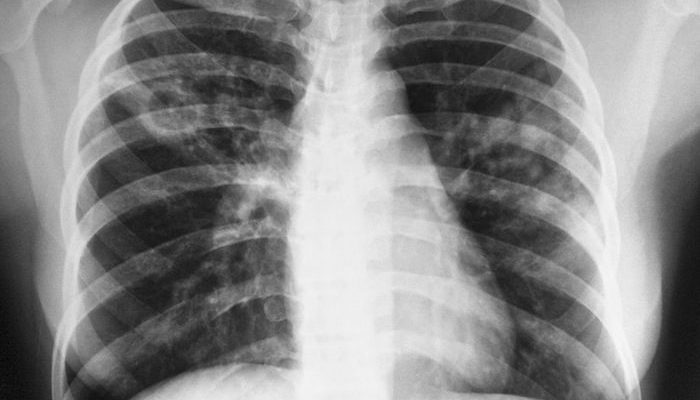

Бронхоальвеолярный инфильтрат на рентгенограмме выглядит как очаговая штриховка в верхней доле неправильной формы, интенсивность небольшая, диаметр не превышает 3 см. Эта область вытянута в сторону корня легкого, контуры ее размыты. Компьютерная томография показывает экссудативное воспаление вокруг небольших разделяющих бронхов, которое образует инфильтрат.

Периферический инфильтрат подходящего оттенка по форме, средней интенсивности и четких контуров.

Инфильтративный туберкулез легких в фазе распада и инфильтрация на рентгенограмме показывает кавернозное просветление в центре инфильтрата, а в нижних частях видны очаги бронхогенного распространения микобактерий.

Мутный инфильтрат на рентгеновском снимке имеет вид неравномерного затенения, локализованного в одном или нескольких сегментах. Контуры размыты, на пораженном участке могут быть небольшие полости.